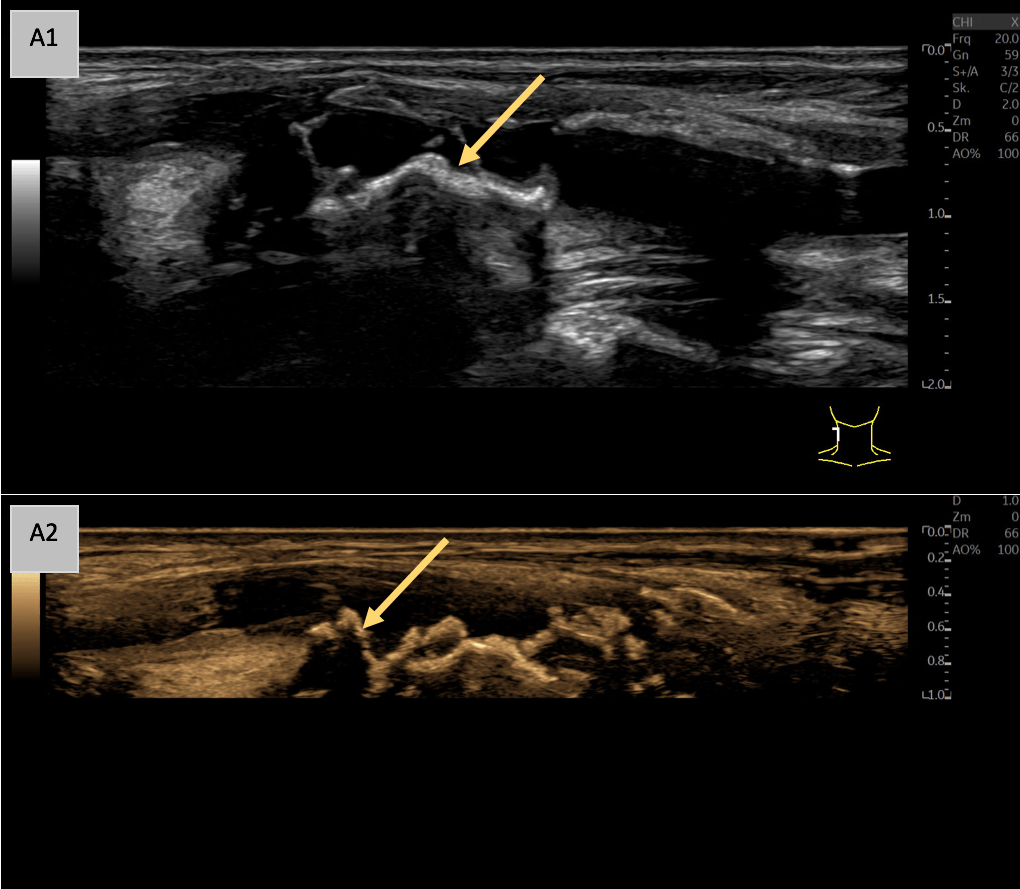

A: B-Mode imaging in the sagittal plane (A1) shows a markedly echogenic and inhomogeneous vessel wall of the common carotid artery with a thickened intima-media complex and irregular echogenic wall changes. Notably, multiple echogenic, wall-adherent formations with partial distal acoustic shadowing are observed (yellow arrow), indicative of significant plaque formation. Speckle Reduction Imaging (SRI) and Cross Beam techniques were employed to optimize the B-Mode image (A2), which is illustrated in sepia for enhanced visualization.